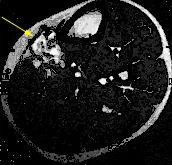

Das linke Bild zeigt die Gefäßmalformation (gelber Pfeil) vor der Therapie. Im rechten Bild unmittelbar nach LITT findet sich eine akute Schwellung und eine Thrombosierung, sichtbar als schwarze Areale innerhalb der Gefäßmalformation (roter Pfeil).